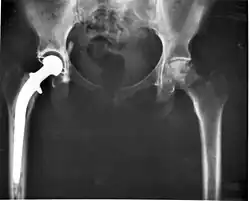

This discovery caused him to begin looking for a slippery substance that could be used for the socket of a total hip replacement operation. Polytetrafluorethylene (PTFE, also known as Teflon) seemed to meet this requirement. After some apparently successful experiments with the material, he adopted it for his hip replacement surgeries. They were carried out as follows: discarding the head of the femur; replacing it with a metallic implant that was fixed with acrylic cement; and, using a PTFE acetabular socket, insertion of the implant into the acetabulum.[28]

His determination pushed him to seek an alternate material. He continued to test various materials, until a salesman approached him offering Ultra-high-molecular-weight polyethylene (UHMWPE), which he rejected because of his lack of understanding of the problem; his assistant told him privately that he would endeavor to test it.[30] It was serendipity, and he immediately grasped the potential of the HMWP; after some tests, Charnley implanted it for the first time in November 1962.[31] Mindful of his previous failure with the PTFE socket, he waited for a year, during which time he carefully observed the status of his patients. Five years later, when he was convinced that HMWP was a safe material, he announced his discovery, making it possible for other surgeons to use it.[32] As time went by, the number of operations increased, and Charnley designed a machine which mechanically built prostheses and sockets, as well as an apparatus for evaluating patients for their hip disorders before and after the operation.[33]